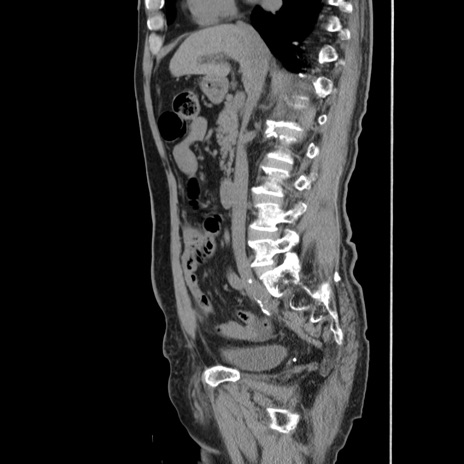

症例24(矢状断像)

【症例】80歳代男性

【主訴】左側腹部痛、嘔吐

【現病歴】本日早朝より左腹部に痛みあり。昼頃嘔吐認めたため、救急要請。

【既往歴】直腸癌(Mile手術)、胆摘

【身体所見】意識清明、BT 35.9℃、BP 221/93mmHg、SpO2 97%(RA) 、腹部:左ストーマ周囲に限局性の腹部膨隆あり。 膨隆部自発痛・圧痛あり・軟。

【データ】WBC 7700、CRP 0.09